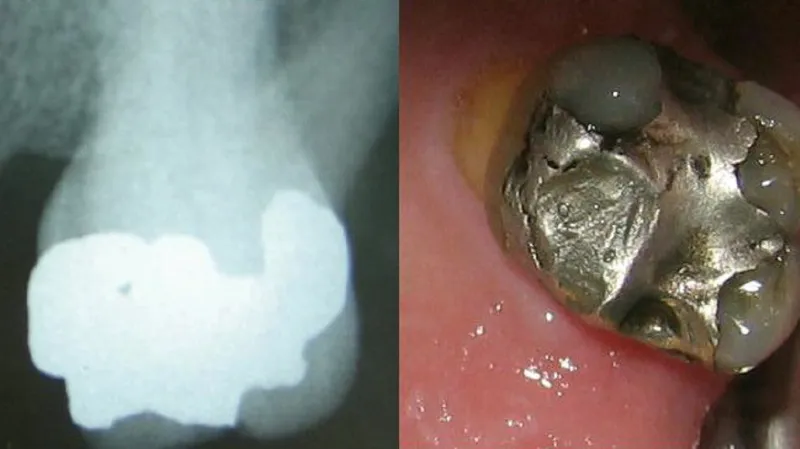

Amalgámové plomby se používají bezmála dvě stě let. Přestože neexistují silné důkazy, že by přímo škodily, jejich používání se omezuje.

Amalgámové plomby se používají v zubní medicíně vlastně už od roku 1826, kdy je vymyslel francouzský lékař Auguste Taveau. Jakmile se rozšířily, staly se jedním z nejpoužívanějších výrobků medicíny – podle studie z roku 2014 bylo ročně aplikováno asi 100 milionů těchto plomb.